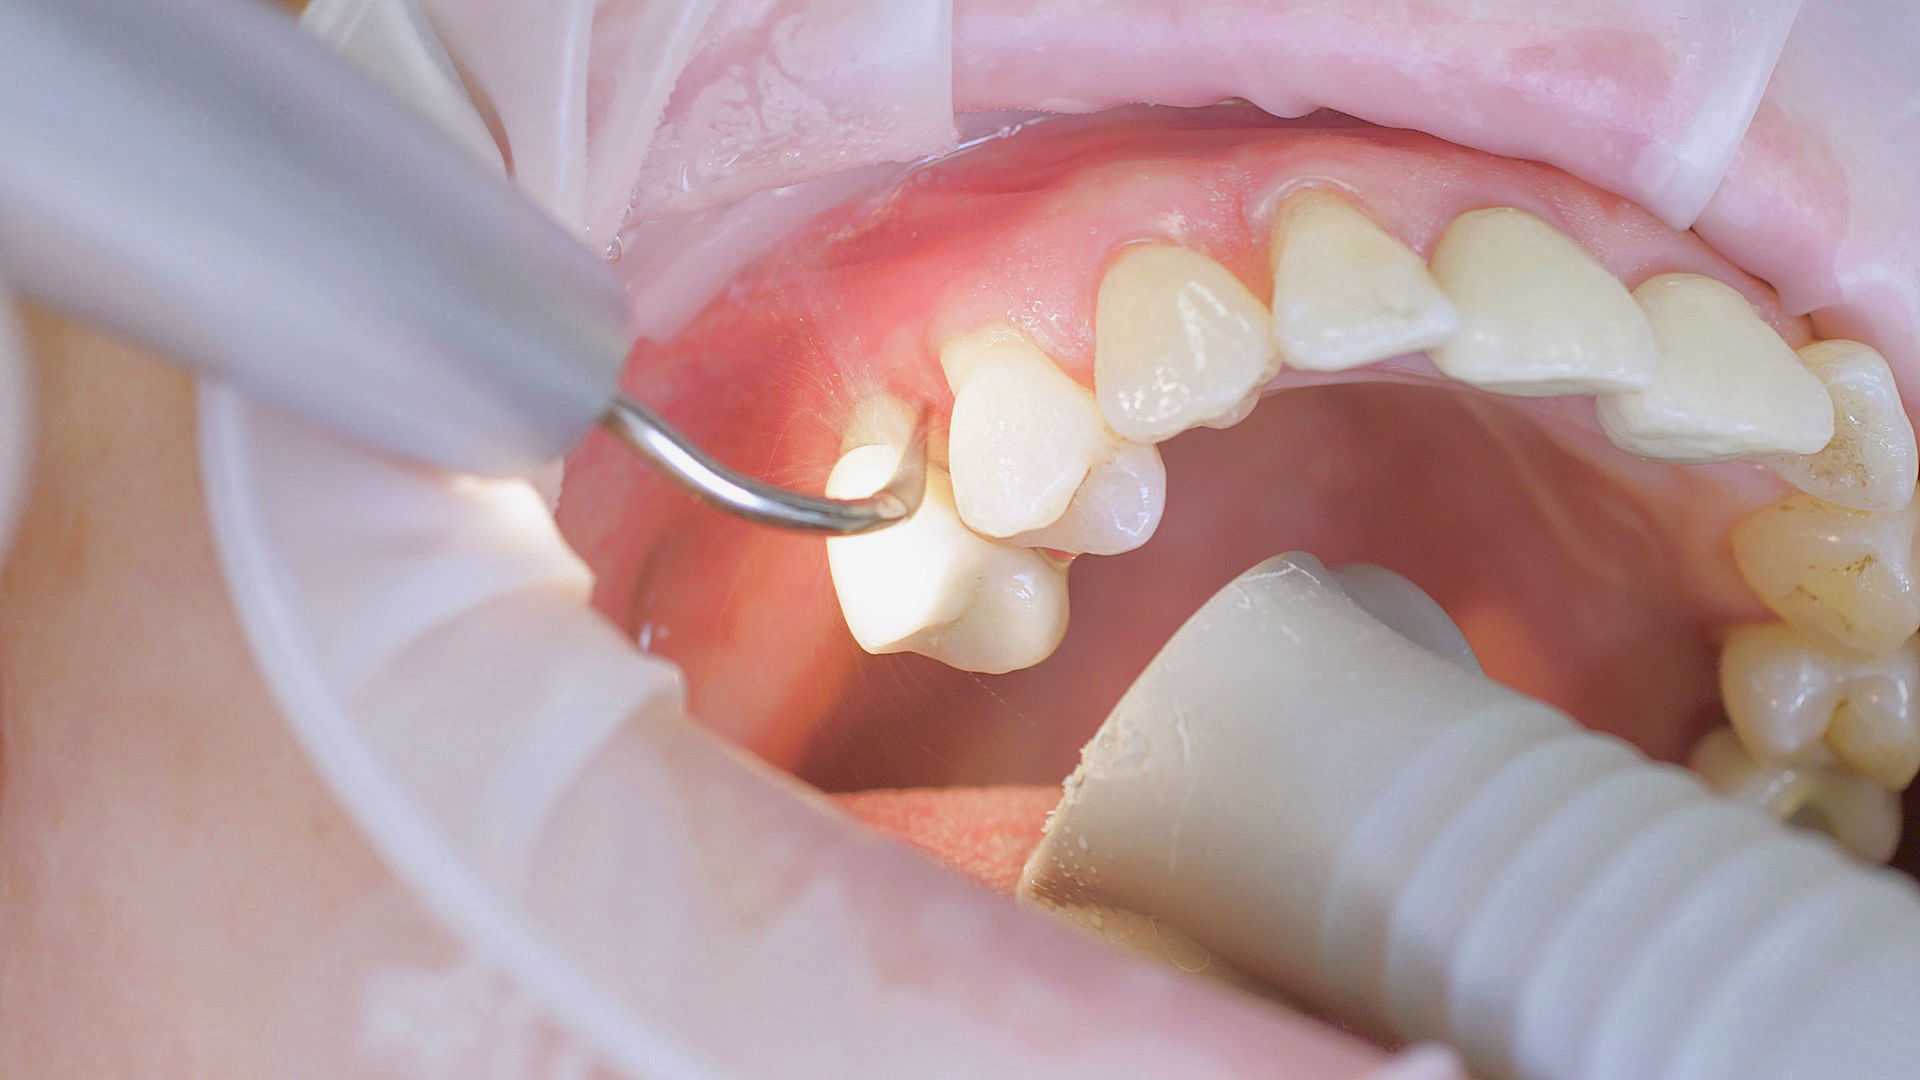

Every dental examination is based on a detailed medical history combined with targeted diagnostics con- taining as much detail as possible: The dentist records systemic risk factors such as diabetes or smoking and identifies any potential increased tendency to inflammation.[3] Hard and soft tissues are examined and periodontal pockets are probed in a screening test according to PSR (Periodontal Screening and Recording). In case of abnormal findings, the periodontal status is then re- corded and therapy is initiated where necessary. This treatment begins with professional biofilm management, by using, for example, rotary cups and polishing com pounds (Fig. 1), and comprehensive instructions in oral hygiene. Sonic or ultrasonic systems remain an effective alternative or supplement to manual instruments for sub- gingival debridement and biofilm management (presentation by Prof. Dr Ulrich Schlagenhauf;